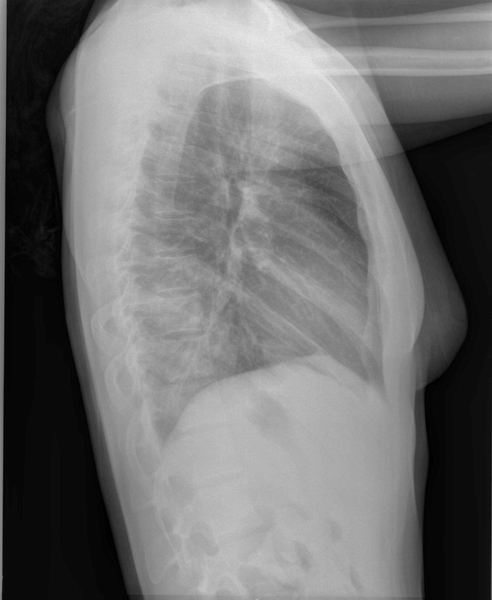

Thorax